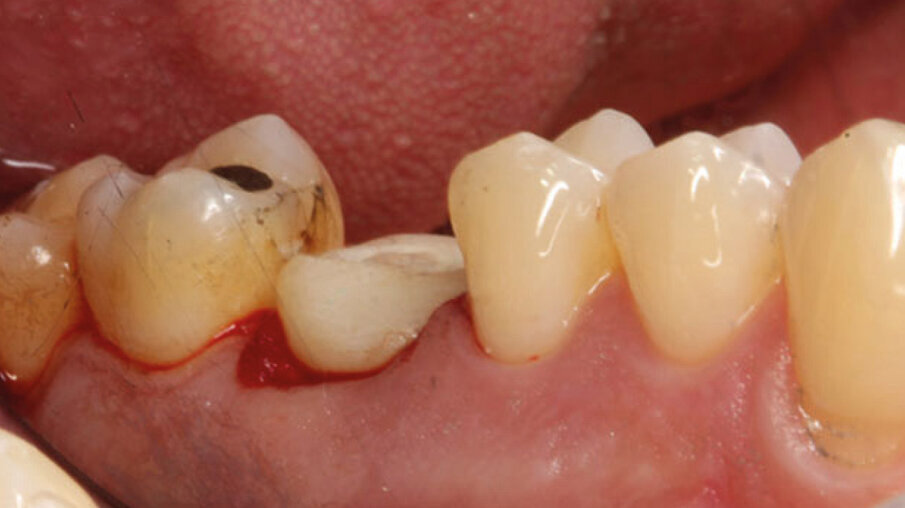

Un paziente maschio (ASA I), senza patologie croniche sistemiche e non fumatore, è stato sottoposto all’estrazione dell’elemento 16 a seguito del fallimento di terapie endodontiche e dell’impossibilità di eseguire un restauro coronale (Figg. 1a, 1b). Nella selezione del paziente sono stati criteri di esclusione: pregressa radioterapia nel distretto testa/collo, assunzione di farmaci che possano indurre ONJ, disordini ematici coagulativi, bruxismo, scarsa igiene orale domiciliare, occlusione instabile, carie non trattate, malattia parodontale non controllata, denti adiacenti a quelli da estrarre con mobilità di grado I o superiore, aspettative di risultato irreali, impossibilità o non propensi a tornare ai controlli di routine e di follow-up. La situazione dei tessuti è stata valutata pre-operatoriamente tramite radiografia periapicala (Fig. 1c) (VistaScan Mini Plus, Dürr Dental). Tramite la CBCT pre-operatoria è stato possibile fare una programmazione implantare. Sulla base dell’anatomia coronale è stata definita la posizione implantare (OnDemand3D, Cybermed), da questa analisi sono stati decisi anche il diametro e la lunghezza dell’impianto.

Fig. 1a_Foto iniziale occlusale.

Fig. 1b_Foto iniziale vestibolare.